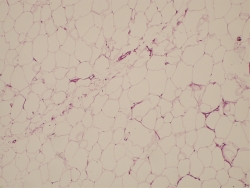

Para realizar un correcto tratamiento es necesario identificar la etiología y, solo en caso de no tener un diagnóstico de certeza, vamos a reconocer la artrofibrosis como causa de la rigidez, como un proceso de metaplasia del fibrocartílago con incremento de la fibrosis intersticial(13)(14)(Figuras 2 y 3). La historia clínica ayuda a pensar en los problemas de cicatrización, la presencia de infección superficial en el postoperatorio inmediato, los traumatismos y en la aparición de una rigidez(15)(16). Un cuadro que aparece en el postoperatorio inmediato lleva a pensar que se trata de un error quirúrgico o una rehabilitación inadecuada, mientras que en el caso de una rigidez de aparición tardía, tras un periodo de movilidad satisfactoria, nos encaminará a un proceso de infección latente o descementación.

Figura 2. Patrón intersticial normal de la grasa de Hoffa.

Figura 3. Patrón de fibrosis intersticial del paquete adiposo de Hoffa en rodilla rígida.